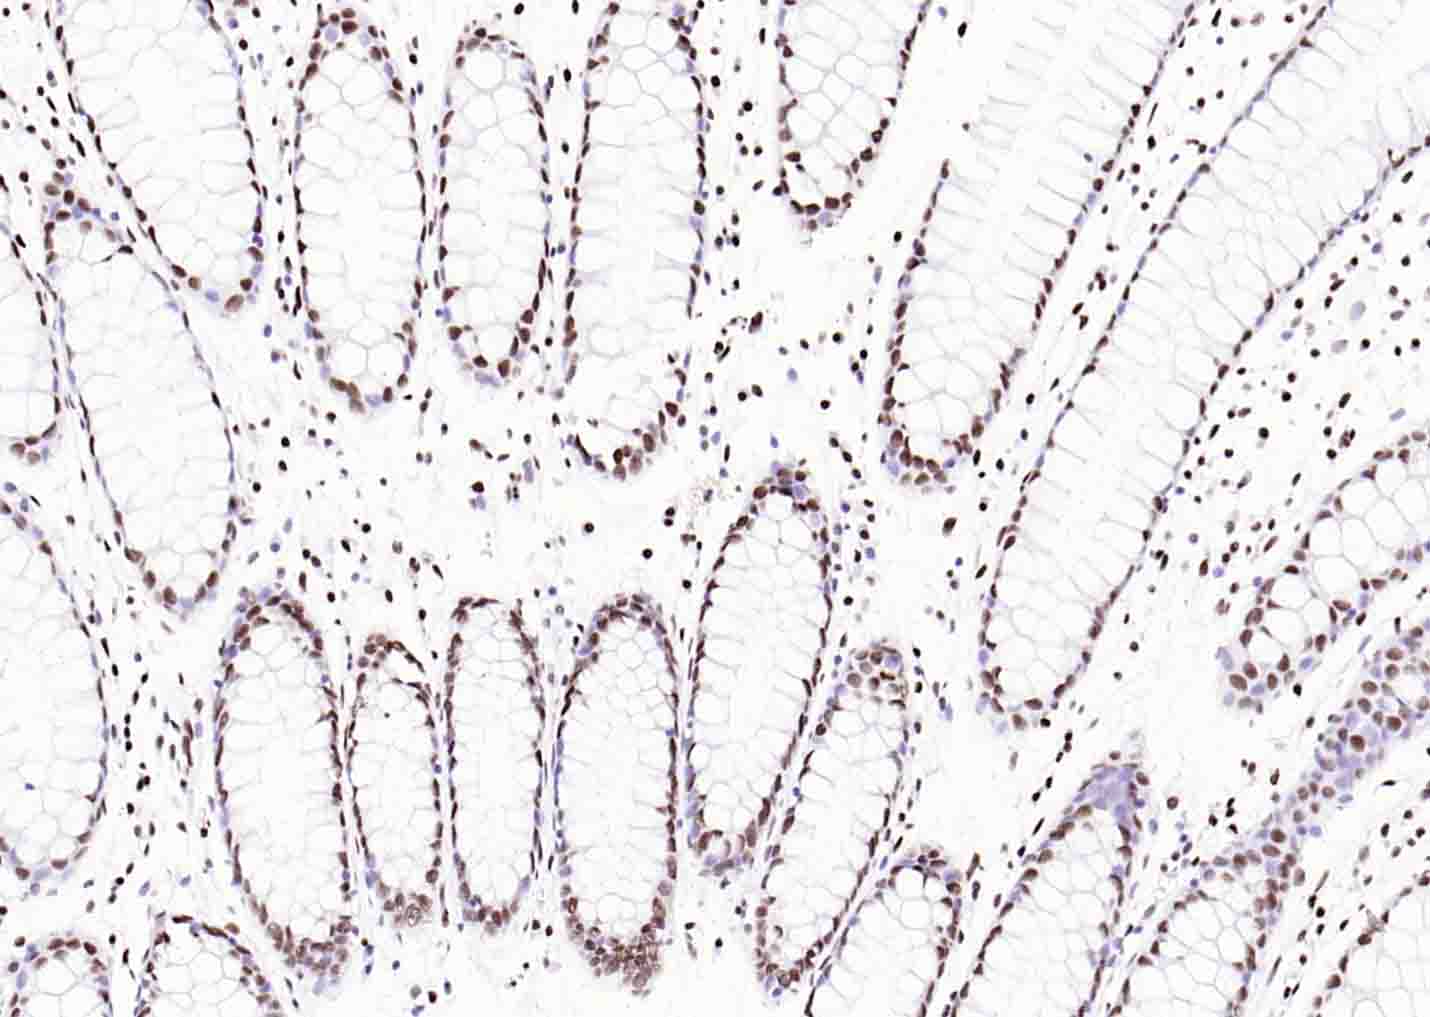

对照切片(大鼠脑) |

Histone H3 is one of the DNA-binding proteins found in the chromatin of all eukaryotic cells. H3 along with four core histone proteins binds to DNA forming the structure of the nucleosome. Histones play a central role in transcription regulation, DNA repair, DNA replication and chromosomal stability. Post translationally, histones are modified in a variety of ways to either directly change the chromatin structure or allow for the binding of specific transcription factors. The N-terminal tail of histone H3 protrudes from the globular nucleosome core and can undergo several different types of post-translational modification that influence cellular processes. These modifications include the covalent attachment of methyl or acetyl groups to lysine and arginine amino acids and the phosphorylation of serine or threonine.

用吸水纸吸去玻片上多余的液体,加入2-4滴大鼠Histone H3 鼠单抗工作液(试剂5),置于湿盒中,4℃孵育过夜或37℃孵育1-2 h。

*5. 发表论文时引用本产品的写作建议 "IHC0111R, Bioss Antibodies"。引用示例: “Rat tissue sections using Rat Histone H3 IHC Kit (IHC0111R, Bioss Antibodies) were stained for Histone H3 according to the manufacturer's instructions.”